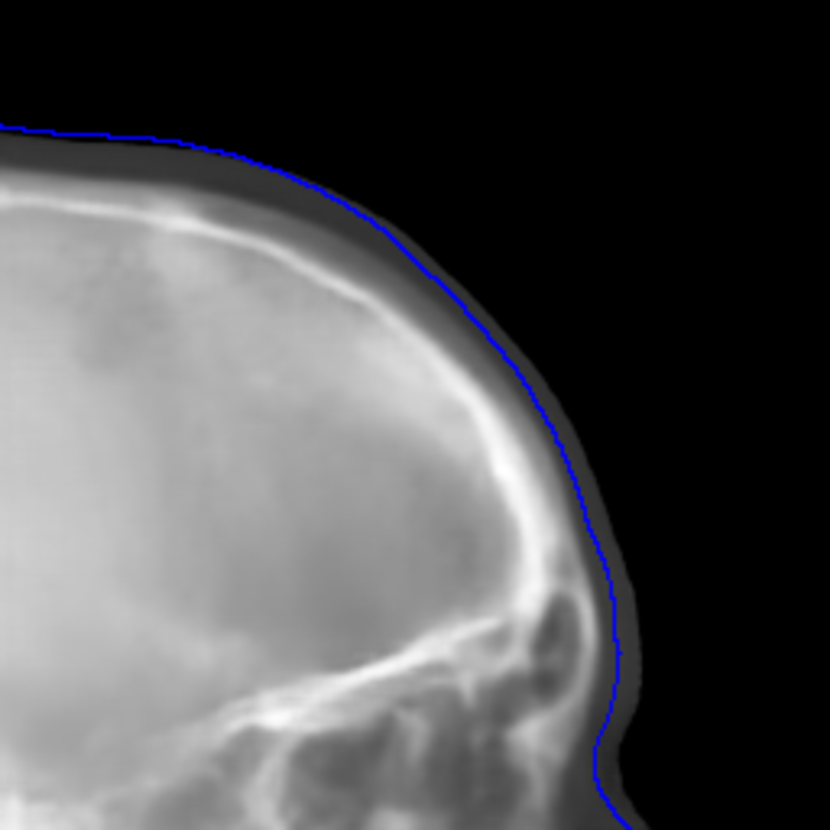

Refer to caption

(a) Real cephalogram

(b) Synthetic cephalogram

(c) Plot of samples and sigmoid curves

Fig. 2: Image contrast difference between real conventional cephalograms and RayCast synthetic cephalograms: (a) a real cephalogram example; (b) a RayCast synthetic cephalogram example; (c) the plot of samples between RayCast synthetic cephalograms and real cephalograms with an original sigmoid curve (red) and our proposed modified sigmoid curve (blue).

In Fig. 2, one real conventional cephalogram example and one example of 𝒈𝒈\boldsymbol{g} are displayed, where evident image contrast difference between these two images is observed. It is because the X-ray films used in conventional cephalograms have the special nonlinear optical property that the characteristic curve between optical density and logarithmized X-ray exposure has a sigmoid-like shape [42]. According to the Lambert-Beer law, the logarithmized X-ray exposure is equivalent to the attenuation integral. It indicates that the intensity relation between the desired cephalogram and the attenuation integral image 𝒈𝒈\boldsymbol{g} should also exhibit a sigmoid-like curve. Therefore, to make the image contrast of synthetic cephalograms similar to conventional cephalograms, a sigmoid intensity transform is necessary.

where the intensity transform is a modified sigmoid function, illustrated as the blue-dotted curve in Fig. 2.